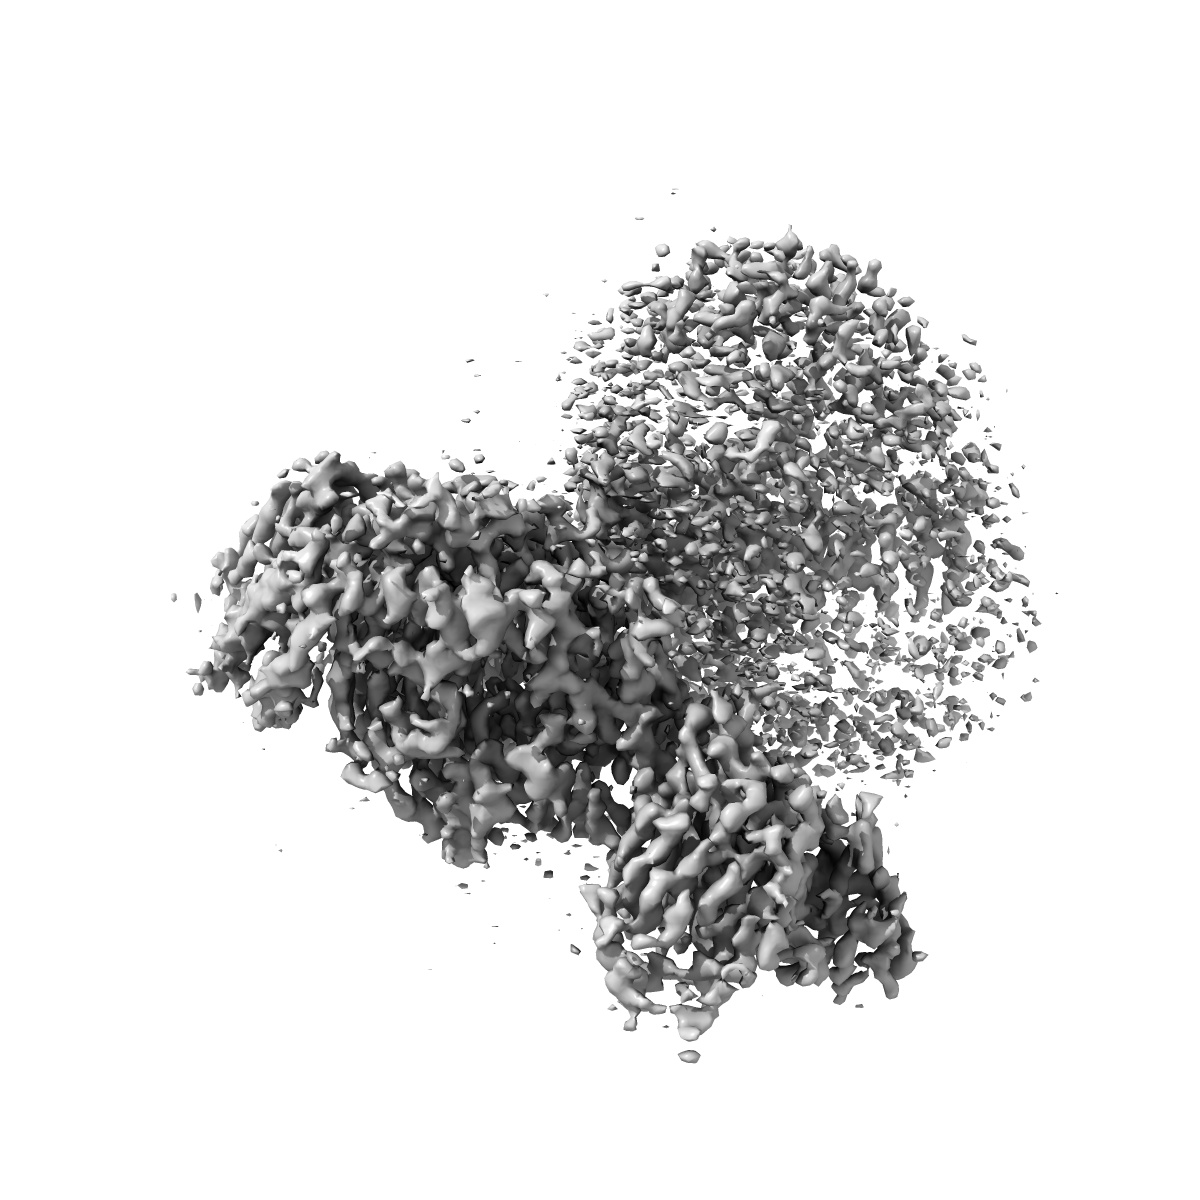

cryo-EM of human Glucagon-like peptide 1 receptor GLP-1R in apo form

Single-particle3.2 Å

Sample: cryo-EM of apo form human Glucagon-like peptide 1 receptor GLP-1R, trimeric G protein complex and stabilizing antibodies